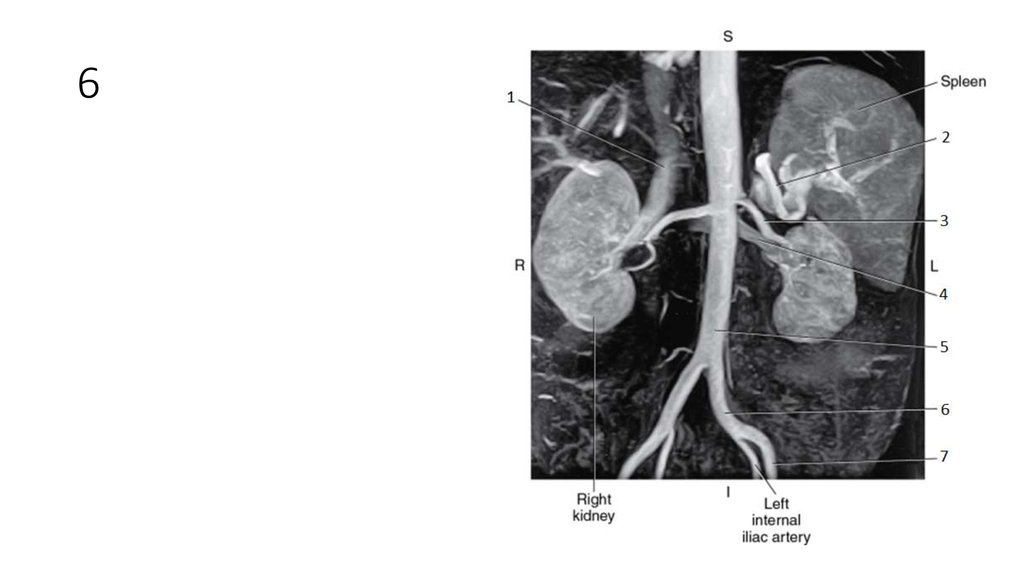

62. 1

63. 1

• Inferior Vena Cava (IVC)

64. 2

65. 2

• Splenic Artery

66. 3

67. 3

• Left Renal Artery

68. 4

69. 4

• Left Renal Vein

70. 5

71. 5

• Aorta

72. 6

73. 6

• Left Common Iliac Artery

74. 7

75. 7

• Left External Iliac Artery